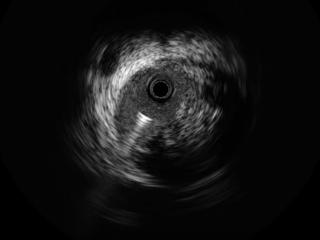

技术突破!青岛西海岸第二院脑血管病科成功开展山东省内首例 “应用IVUS指导下精准颈动脉狭窄介入治疗”